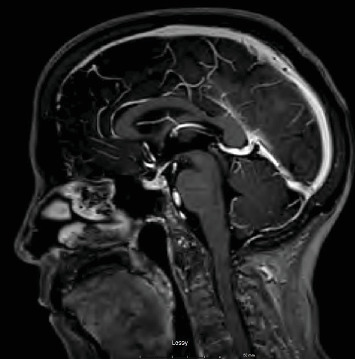

Abstract Image

Immune checkpoint inhibitors have revolutionized cancer treatment, yet their use is associated with unique and sometimes unpredictable immune-related adverse events. We present a case of a 67-year-old female with renal cell cancer treated with ipilimumab and nivolumab who developed aseptic meningitis and hypophysitis. This case highlights the challenges in managing immune-related adverse events and underscores the need for vigilance in monitoring patients receiving ICIs.